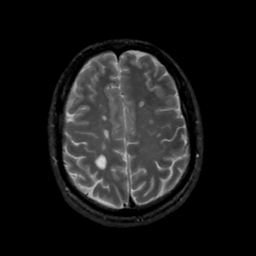

MR Study #15, June 9, 1991 -- Slice #37

[Home][Help][Clinical][Tour 1][Tour 2] Slice 37